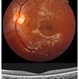

- ILM peel, ILM flaps, induction

- This video demonstrates, PVD induction , followed by ILM peeling in multiple flower petal flap technique.